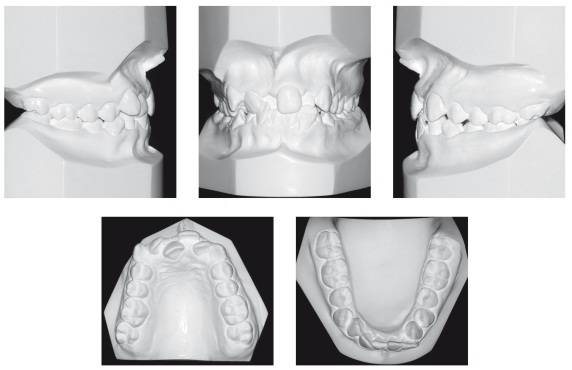

放射检查:一般包括X线头影测量片、曲面体层片和CBCT(锥束CT)。有时还包括其他放射检查,比如螺旋CT等。通过放射检查,医生可以看到骨骼及牙齿的形态、位置及发育状况,以及是否有牙体、根尖周、牙周疾病等,从而评估是否需要正畸治疗、进行何种治疗。

(摘自“第三章第一节正畸的基本知识”)

头影测量片(上)、曲面体层片(中)和锥束CT(下)